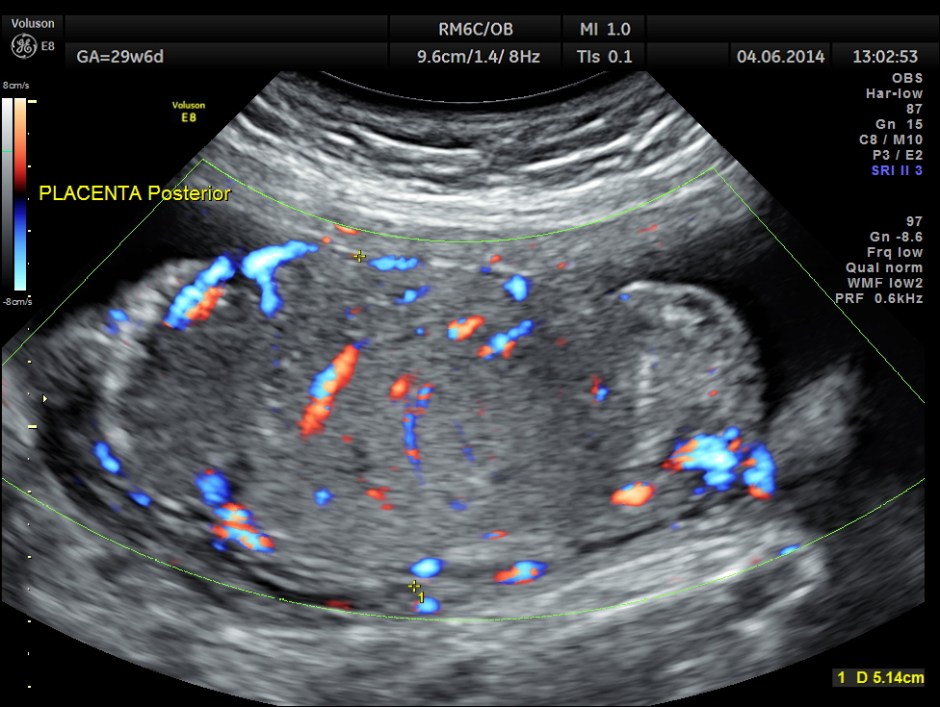

She had a thick placenta , but appears homogenous.

Umbilical artery P.I and R.I are high . The MCA / UMBILICAL arterial ratio is abnormal.

But the doppler values are abnormal. Umbilical artery P.I. and R.I are > 95 % tile . MCA P.I. and R.I are lower .

The cerebroplacental ratio ( MCA/UA ratio ) is abnormally low -0.70 suggestive of utero placental insufficiency.